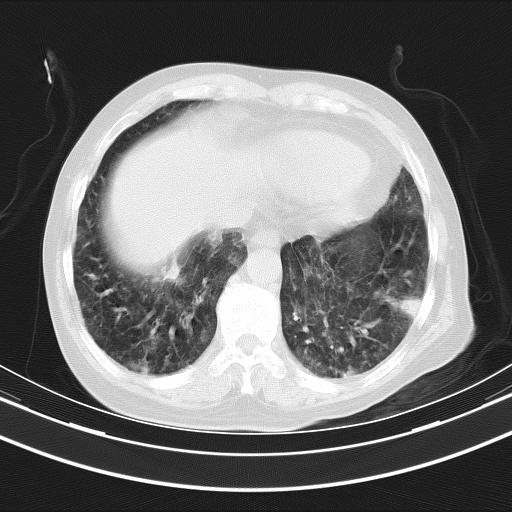

老年女性,嗜睡3天,意识模糊。轻咳,无发热。

双肺多发淡片影,毛玻璃影,,支持支气管肺炎,,建议血气找原因,,嗜睡是否肺性脑病?有没有慢支病史?

1)两肺感染性病变;建议抗炎治疗后复查。2)纵隔淋巴结肿大。3)左侧胸腔积液。

3)左侧胸腔积液。